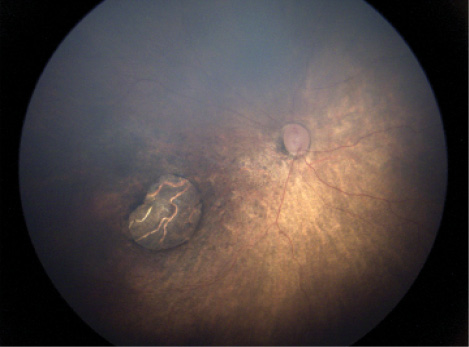

Figure 1. Fundus image showing optic nerve hypoplasia and pallor, chorioretinal scar, and retinal pigmentary changes in the macular region, with vascular attenuation.

The Zika virus (ZIKV) is a flavivirus that is mainly transmitted by Aedes aegypti, one of the most common mosquitoes worldwide, also responsible for spreading dengue, chikungunya, yellow fever, and West Nile virus.1 The emergence of ZIKV has caused great alarm in many countries because of its capacity to cause microcephaly in newborns, along with other malformations, including hearing loss, limb anomalies, and ocular findings (Figure 1), which characterize a new clinical condition called congenital Zika syndrome (CZS).2